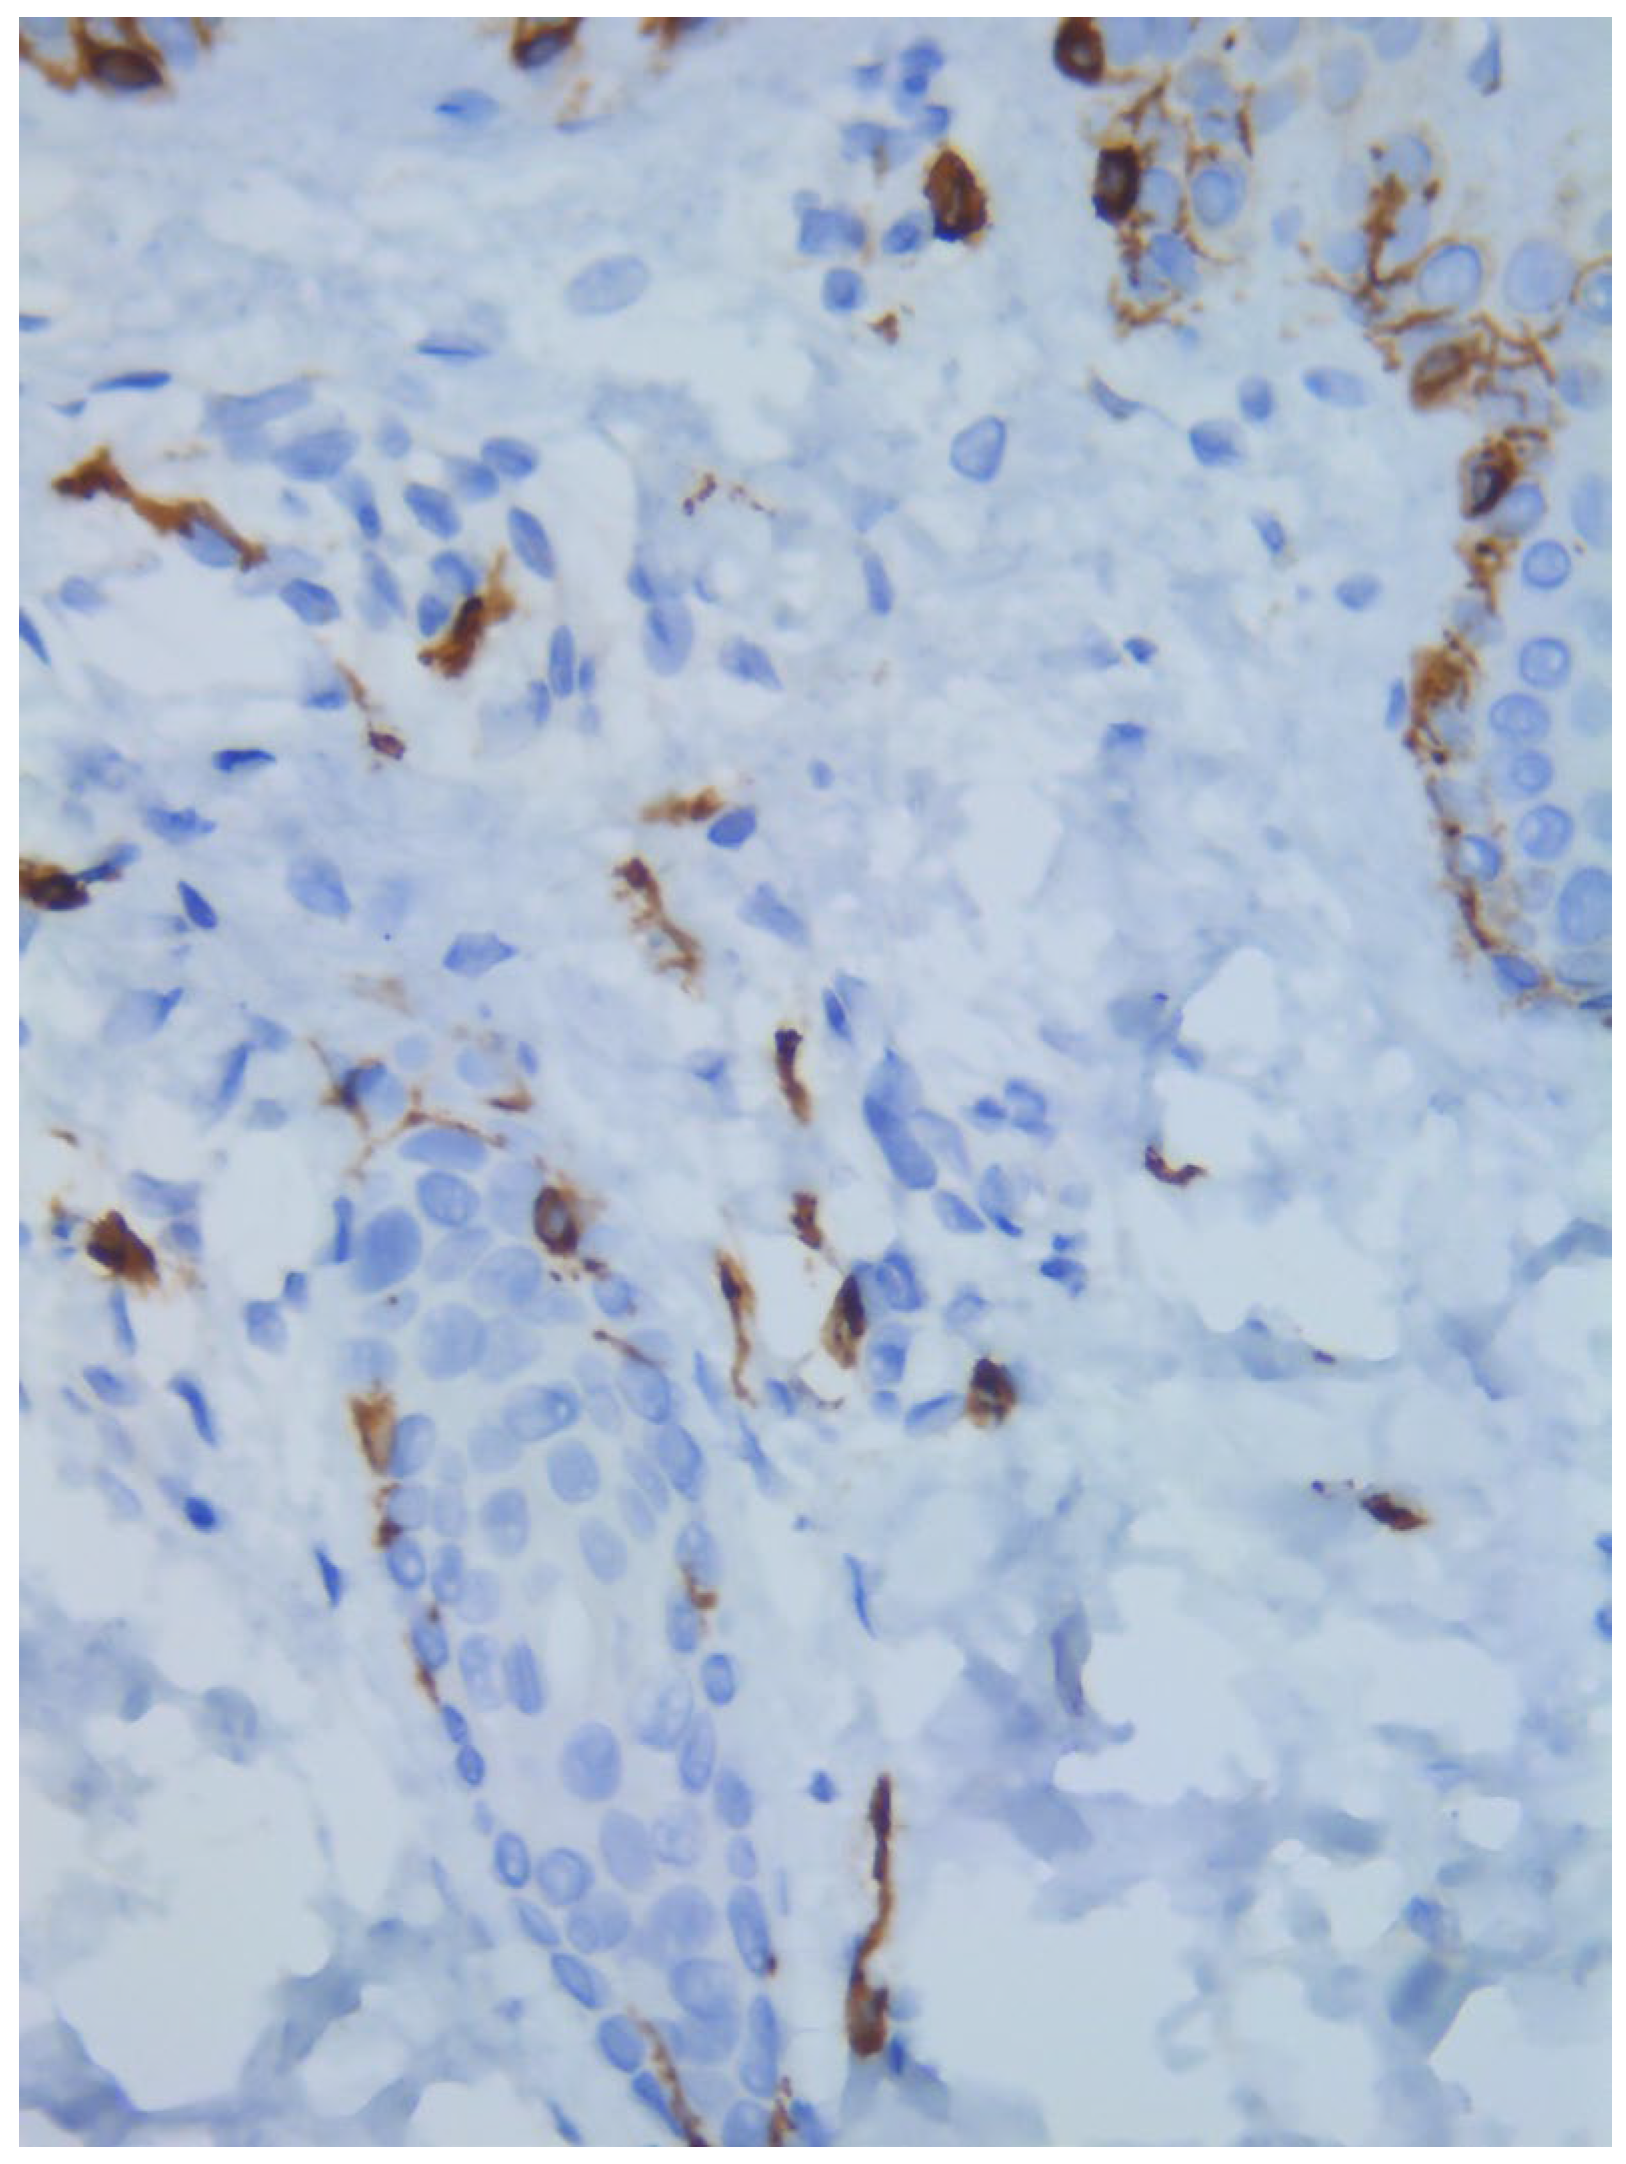

Two skin samples were taken from the upper and lower back, both showing slight, basal cell hyperpigmentation and an inflammatory infiltrate in the superficial dermis (Figure 3). Immunohistochemical stains with tryptase and CD117 showed that the infiltrate included mast cells (Figure 4), mostly with perivascular distribution. Mast cell count in six samples ranged from 11 to 12 mast cells per high-power view (CD117 and tryptase, respectively). The count per mm2 showed 34 mast cells with tryptase and 48 with CD117. C-kitD816V mutation analysis was not available. The bone scintigram did not detect any alterations and an abdominal ultrasound ruled out visceromegaly and only showed 10 mesenteric lymph nodes of non-specific appearance. He is currently under control and receiving oral levocetirizine 5 mg at night.

Figure 4. Mast cell infiltration (CD117, ×400).